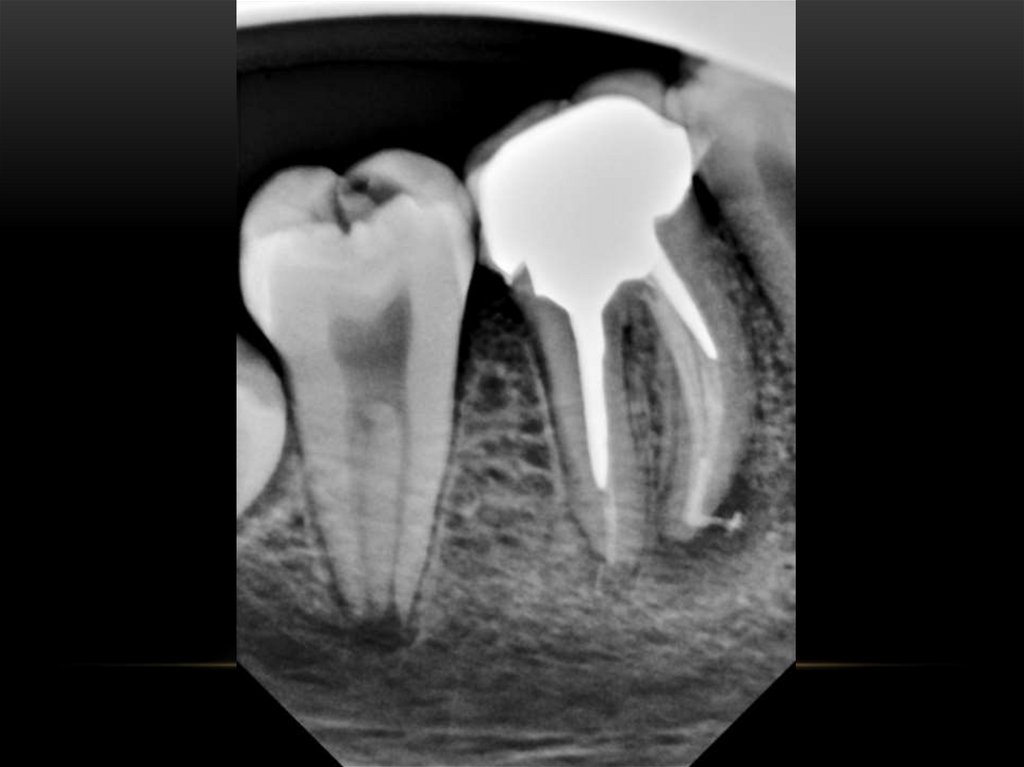

Механическая обработка корневых каналов. Этапы эндодонтического лечения

Методики пломбирования корневых каналов

Пломбирование корневых каналов зуба

Анатомия корневых каналов

Лечение корневых каналов